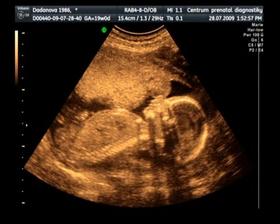

Naše maličké

Dne 15. 12. v 5:40 se nám narodil syn Jurášek. Vážil krásných 3500g a měřil ukázkových 50 cm. A je to nejkrásnější kluk na světě : )